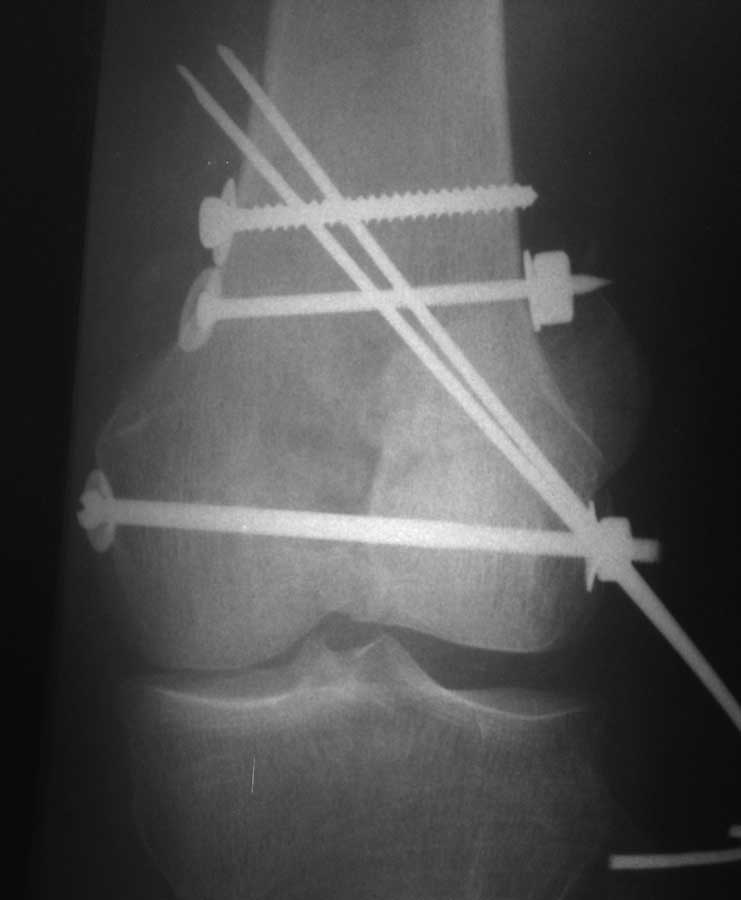

Коллеги, извиняюсь за задержку с результатом. Через медиальную артротомию обнажили н/3 бедра, отрепонировали внутренний мыщелок, затем по нему сопоставили суставную поверхность бедра с латеральным мыщелком.

Больная выписана в ортезе с регулируемым углом сгибания в колене, с рекомендациями через 3 нед. удалить спицы и начать разрабатывать сустав.